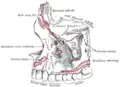

Interior da superfície lateral. Superfície lateral esquematizada.

Superfície lateral esquematizada. Superfície medial esquematizada.